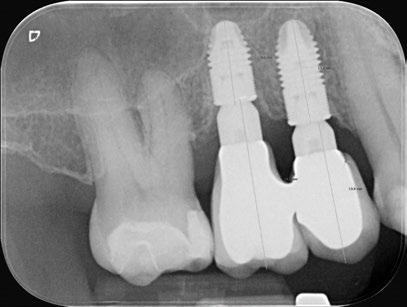

3. Fase quirúrgica final

A los 6 meses de cicatrización, se realizó un nuevo CBCT, obteniendo un nuevo archivo DICOM que alineamos con el STL del encerado. De esta manera, se planificó la posición de los implantes a 4 mm del margen de la restauración final y se diseñó y confeccionó la férula de cirugía guiada dentosoportada en 12-13 y 22-23, la cual imprimimos con la impresora 3D Formlabs®. El provisional

de carga inmediata lo diseñamos con el programa de diseño 3D Exocad® a partir del encerado y se imprimió también en clínica con la misma impresora 3D (Figuras 14-16).

La cirugía se realizó bajo sedación consciente y anestesia local (articaína 4% con epinefrina 40/0,01 mg/ml Ultracain®, 5 carpules en vestibular y palatino de la arcada superior). En primer lugar, se realizaron las exodoncias de los dientes remanentes 11, 21 y 24 y, a continuación, se adaptó la férula de cirugía guiada dentosoportada, insertando los implantes elegidos, en este caso en las posiciones 11 y 21 de Zimvie Tapered Screw-Vent Z3D de 3,7 por 13 mm, 14 Zimvie Tapered Screw-Vent Z3D de 3,7 por 13 mm y 16, 24 y 26 de Zimvie Tapered Screw-Vent Z3D de 4,7 por 13 mm, quedando todos ellos a un torque mayor a 30 Nm. Posteriormente, se realizaron el resto de exodoncias,

Seguidamente, se colocaron los pilares cónicos TSV-TM de Zimmer® y se atornillaron los pilares provisionales de titanio (Figuras 17-23).

Figura 27. Ortopantomografía del provisional atornillado en boca para verificar ajuste.

ortopantomografía de verificación del ajuste pasivo de todos los implantes. Por último, tapamos las chimeneas con teflón y resina provisional y se chequeó nuevamente la oclusión, dando nuevamente las instrucciones de higiene y mantenimiento de la prótesis provisional (Figuras 24-27).